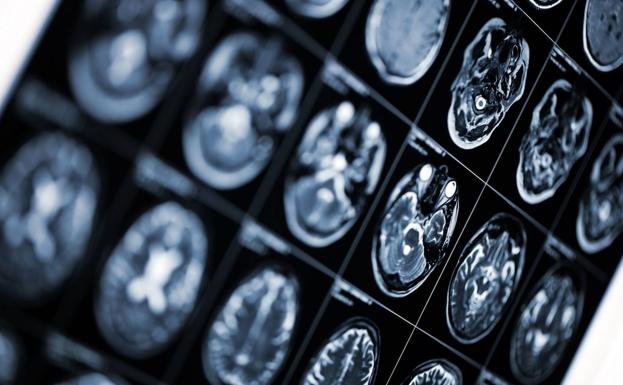

Gobierno y autonomías aprueban el primer plan nacional contra el alzhéimer

La estrategia 2019-2023, que no cuenta con una financiación específica, busca mejorar el diagnóstico precoz y la atención a los enfermos y los familiares que les cuidan